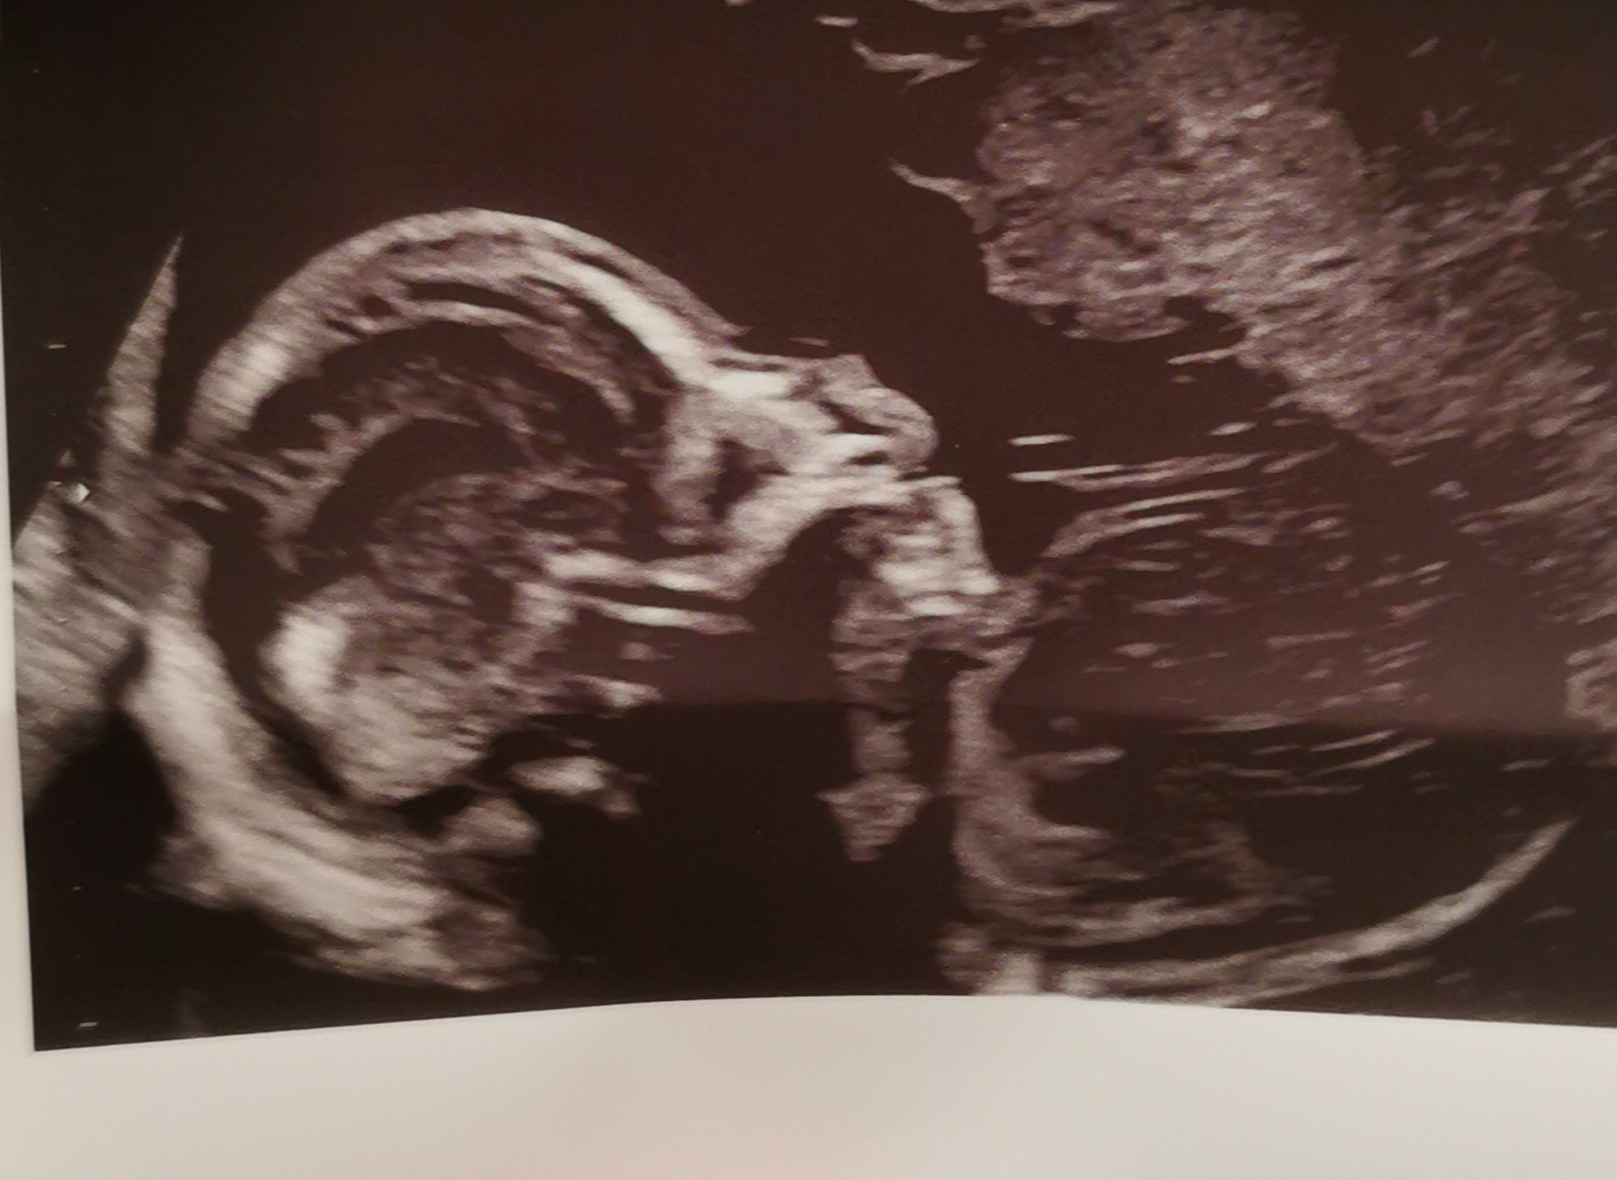

Rudylisek wrote:Ja też melduję się po wizycie 🙂

Dzidzia rośnie zdrowo, 277 g. No i okazało się że będzie drugi chłopczyk🩵 . A ja byłam niemal pewna, że będzie dziewczynka, bo wcześniej dostaliśmy taką informację że pewnie tak będzie 😅

https://zapodaj.net/plik-efgB6HLOJm

Rudylisek piękny dzidziak 🩵

@rudylisek piękny chłopczyk 😍